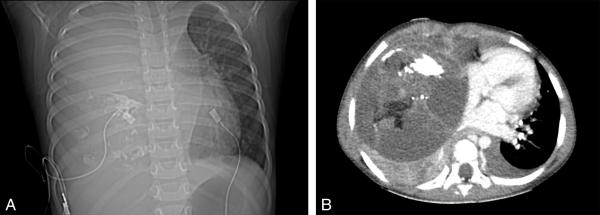

Fig. 60.3.

Tératome.

A. Radiographie de thorax. Volumineuse masse de densité hydrique occupant l’hémithorax droit, contenant des éléments calcifiés, refoulant le médiastin vers la gauche.

B. TDM thoracique, injectée. Volumineuse masse refoulant la masse cardiaque vers la gauche, contenant des éléments hydriques, calcifiés et graisseux affirmant le diagnostic de tératome ; épanchement pleural liquidien gauche, parenchyme pulmonaire droit tassé vers l’arrière.